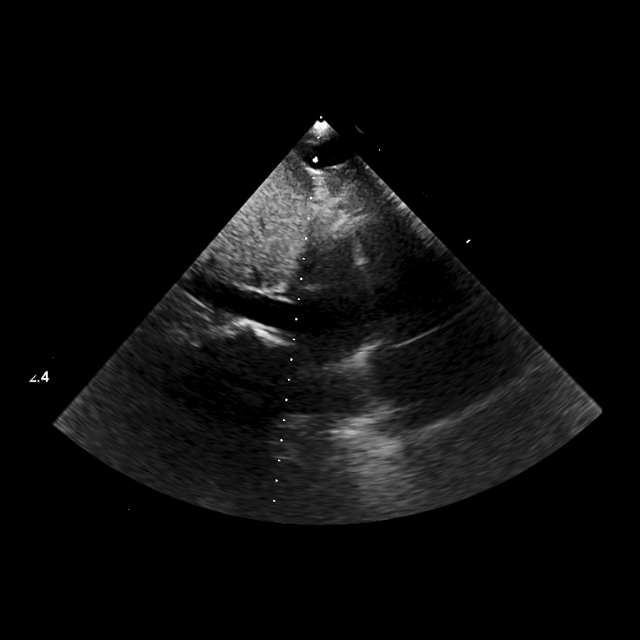

View and measurement extraction

We structure each study to mirror clinical reading: a pretrained classifier assigns standardized views, followed by quantitative measurement extraction. Views are categorized using the American Society of Echocardiography (ASE)–defined classes (mitchell2019guidelines). To extract quantitative parameters, we crop the clinically annotated measurement overlays from the image and transcribe them into structured JSON using Qwen2.5-VL-72B (qwen2.5-VL; Qwen2VL). The resulting fields include chamber dimensions, transvalvular gradients, and Doppler ratios.(Fig. 2a). Extraction fidelity was verified by manual review.